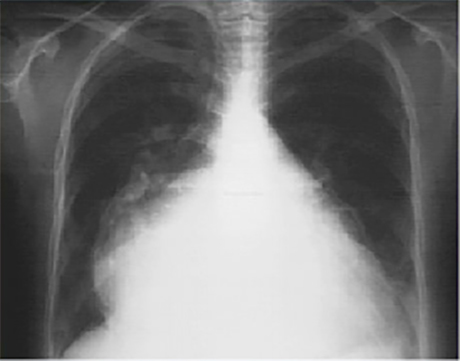

Lat

These chest X rays show marked left atrial enlargement.

In this PA view, the marked left atrial enlargement is demonstrated by the atrial appendage along the left heart border, and is so massive, that it also comprises the right heart border.

Such a giant left atrium may be seen in severe, chronic mitral regurgitation.